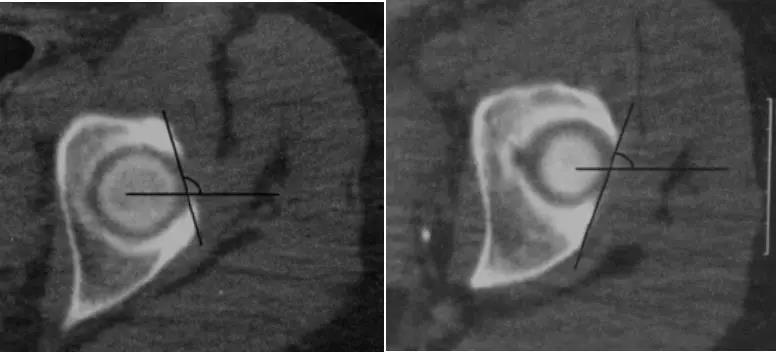

- 横断面显示髋臼后倾:正常髋臼连线与水平线呈钝角;呈锐角,提示髋臼后倾。